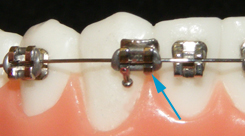

During treatment as your teeth move, it is possible that a wire can protrude from the back braces causing a "poking wire". Placing wax on the wire will help keep you comfortable. Call our office, (619) 421-5060, if you are having an issue with your braces such as this, and schedule a quick appointment to have the wire clipped.